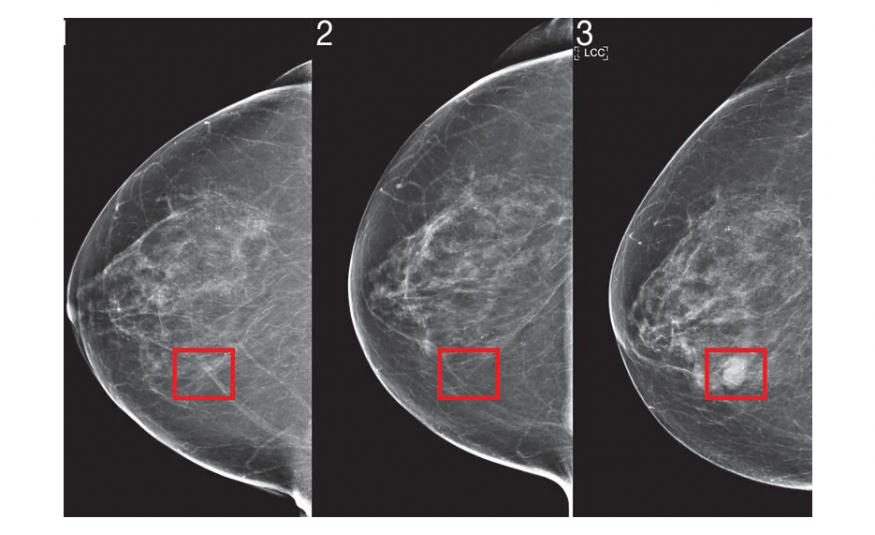

Razvijena umjetna inteligencija koja otkriva rak dojke godinama prije nego što se razvije